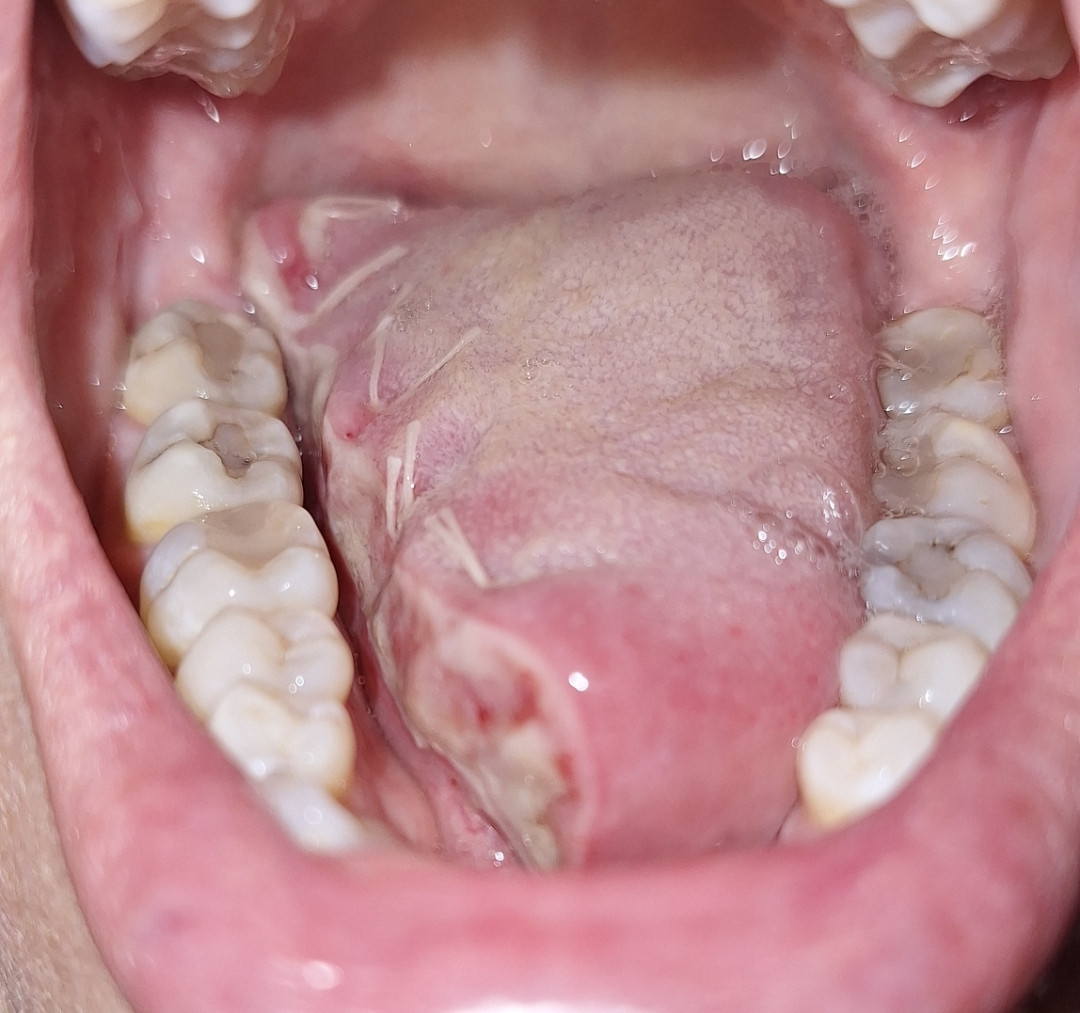

13 juni 2025 ben ik geopereerd aan de plaveiselcelcarcinoom op de tong en de schildwachtklierprocedure is uitgevoerd.

Eenmaal terug op de afdeling ging het best goed. Pijn was minimaal en prima te doen met PCM en Naproxen. Wel veel hoofdpijn door de narcose. Ik had echt de hel verwacht maar dit was echt goed te doen. Praten ging ook best goed. Langzaam en vrij monotoon maar er kwam in ieder geval geluid uit. Heel fijn want dat vond ik toch best spannend. De eerste paar uur durfde ik nog niet de tong te bekijken. Wat zou ik aantreffen? Ze hebben het met een laser weggesneden en vervolgens gehecht. Maar het zag er best oke uit. Ook de hechtingen in de hals zaten netjes in de halslijn. Daar zie je over een tijdje niet meer zoveel van. Maar goed, er moest ook wel weer wat gegeten worden. Wat een spannend moment. Het lukte mij om stukjes brood met jam in stukje van 1cm bij 1cm naar binnen te krijgen en volgens een ritme door te slikken. Na een half uur had ik toch 1 snee brood op! Yes, wat was ik trots!  Veel ijswater en koude thee. Melkachtige producten gaf veel slijmvorming dus die werden even weggelaten. Smootie's waren nog te zuur. Heldere afgekoelde soep deed het ook goed.

Ondertussen ging het herstel thuis best goed. Het eten nam best veel tijd in beslag omdat het vrij langzaam ging. Praten ging best goed. Wel erg wennen dat je een stukje mist. Hij boog wat af naar links en dat probeer je steeds de corrigeren wat natuurlijk niet lukt. Pijn heb ik minimaal gehad. Mijn hals was behoorlijk gezwollen, omvang kalkoen. Maar dit werd in de loop van tijd minder dik en qua kleur trok het weer bij. Doordat ik mogelijk wel wat zenuwen onder de huid zijn geraakt heb ik geen gevoel onder mijn kin.

Toen was het 2 juli, de dag dat de uitslag binnenkwam. Aan het einde van de middag ging de telefoon. De snijmarge van de tong was niet voldoende. Ze hadden verwacht dat de tumor een knobbel zou zijn, de doorsnede was 24mm, het blijkt echter een soort spin te zijn met kleine haartjes die zich verder nestelt. Ze komen bij 1 haartje 2mm te kort van de snijmarge. Echt millimeter werk dus. Als dit het enige zou zijn kun je afwegen om het zo te laten (omdat de snijrand in feite schoon is maar dus niet voldoende) en het vaak te controleren. Echter is er in 1 schildwachtklier toch een uitzaaiing gevonden. Niet schoon dus. Het omliggende gebied in de hals moet dus wederom ook geopereerd worden en verder "schoongemaakt". De arts stond zelf ook te kijken van de uitslag maar zoals hij zelf zegt "Als we nu niks doen staan we over een paar maanden 1-0 achter en is de wedstrijd gespeeld. Nu staan we nog met 1-0 voor en moeten we er voor gaan.... " Dat betekent dat de operatie in een iets kleinere variant weer opnieuw moet voor de tong en er volgt een halsklierdissectie aan de rechterkant. Behoorlijk k#t want de laatste dagen ging het herstel echt wel de goede kant op en de kans op uitzaaiingen was erg klein. Het is en blijft eng dat er zoiets in de lichaam kan groeien wat er niet hoort. De arts verwacht de operatie opnieuw te kunnen uitvoeren op vrijdag 18 juli. Maar ook dit onder voorbehoud. Hopelijk hoor ik volgende week de definitieve datum. Deze zagen we niet helemaal aankomen, de bubbels lagen al klaar in de koelkast en de champagne glazen waren gepoetst. Deze teleurstelling moeten we weer even een plekje gaan geven  en ons weer oppeppen voor de volgende operatie .